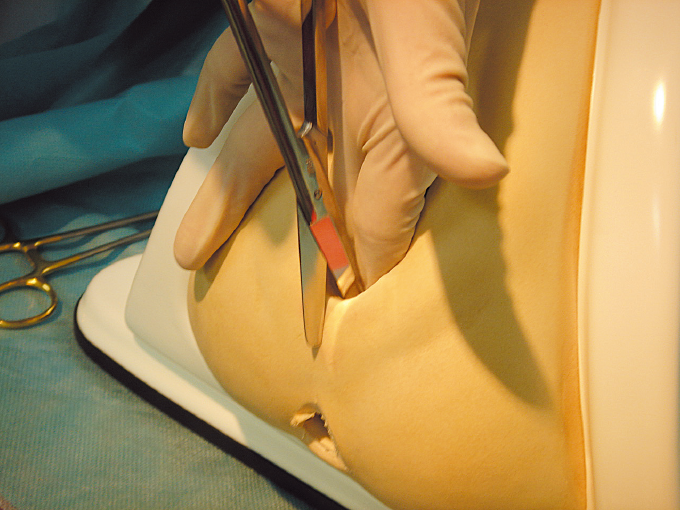

トラブル&ケア日常のトラブル過剰肉芽の物理的切除NPO法人PDN。